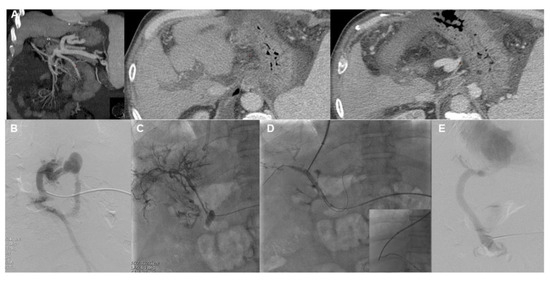

- Chen, Y.; Ye, P.; Li, Y.; Ma, S.; Zhao, J.; Zeng, Q. Percutaneous transhepatic balloon-assisted transjugular intrahepatic portosystemic shunt for chronic, totally occluded, portal vein thrombosis with symptomatic portal hypertension: Procedure technique, safety, and clinical applications. Eur. Radiol. 2015, 25, 3431–3437. [Google Scholar] [CrossRef]

- Entezari, P.; Riaz, A.; Thornburg, B.; Salem, R. Percutaneous Ultrasound-Guided Superior and Inferior Mesenteric Vein Access for Portal Vein Recanalization-Transjugular Intrahepatic Portosystemic Shunt: A Case Series. Cardiovasc. Intervent. Radiol. 2021, 44, 496–499. [Google Scholar] [CrossRef]

- Klinger, C.; Riecken, B.; Schmidt, A.; De Gottardi, A.; Meier, B.; Bosch, J.; Caca, K. Transjugular portal vein recanalization with creation of intrahepatic portosystemic shunt (PVR-TIPS) in patients with chronic non-cirrhotic, non-malignant portal vein thrombosis. Z. Gastroenterol. 2018, 56, 221–237. [Google Scholar] [CrossRef]